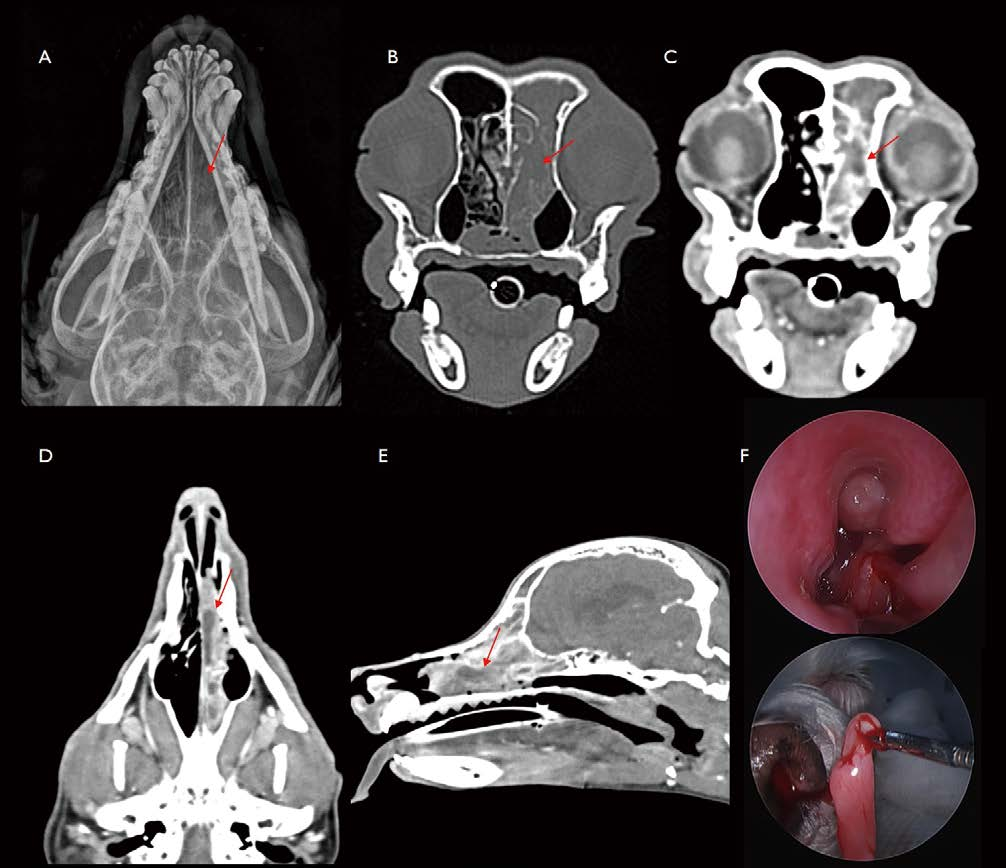

[대한수의사회지 9.png

5살 중성화 암컷 Maltese가 만성 상부 호흡기 증상(상부 폐색성 호흡음, mucopurulent nasal discharge, 개구호흡)으로 내원하였습니다. Plain X-ray에서 choanae 위치에서 연조직 밀도의 음영 및 narrowing 소견이 관찰됩니다(그림 9. A). CT 검사에서 choanae 및 nasopharyngeal space에서 이질적 연조직 밀도의 음영 및 narrowing이 관찰됩니다(그림 9 B C D). Rhinoscopy에서는 choanae 후방으로 심한 점막 부종, 염증성 변화 및 stenotic region이 관찰됩니다. 투시로 Balloon dilation therapy를 실시하였고(그림 9. E), 무마취 CT 모니터링에서(그림 9. F) 환자는 nasopharyngeal stenosis가 해소되어 잘 지내고 있습니다. 환자는 brachycephaly로 어렸을 때부터 쩝쩝거림, 혀를 날름거리는 증상이 있었다는 병력을 미루어 보아, laryngopharyngeal reflux 등의 aerodigestive disorder로 인해 nasopharyngeal stenosis가 발생했을 것으로 고려됩니다. 환자는 dysphagia에 준한 내과적 보존 치료로 현재까지 잘 지내고 있습니다.